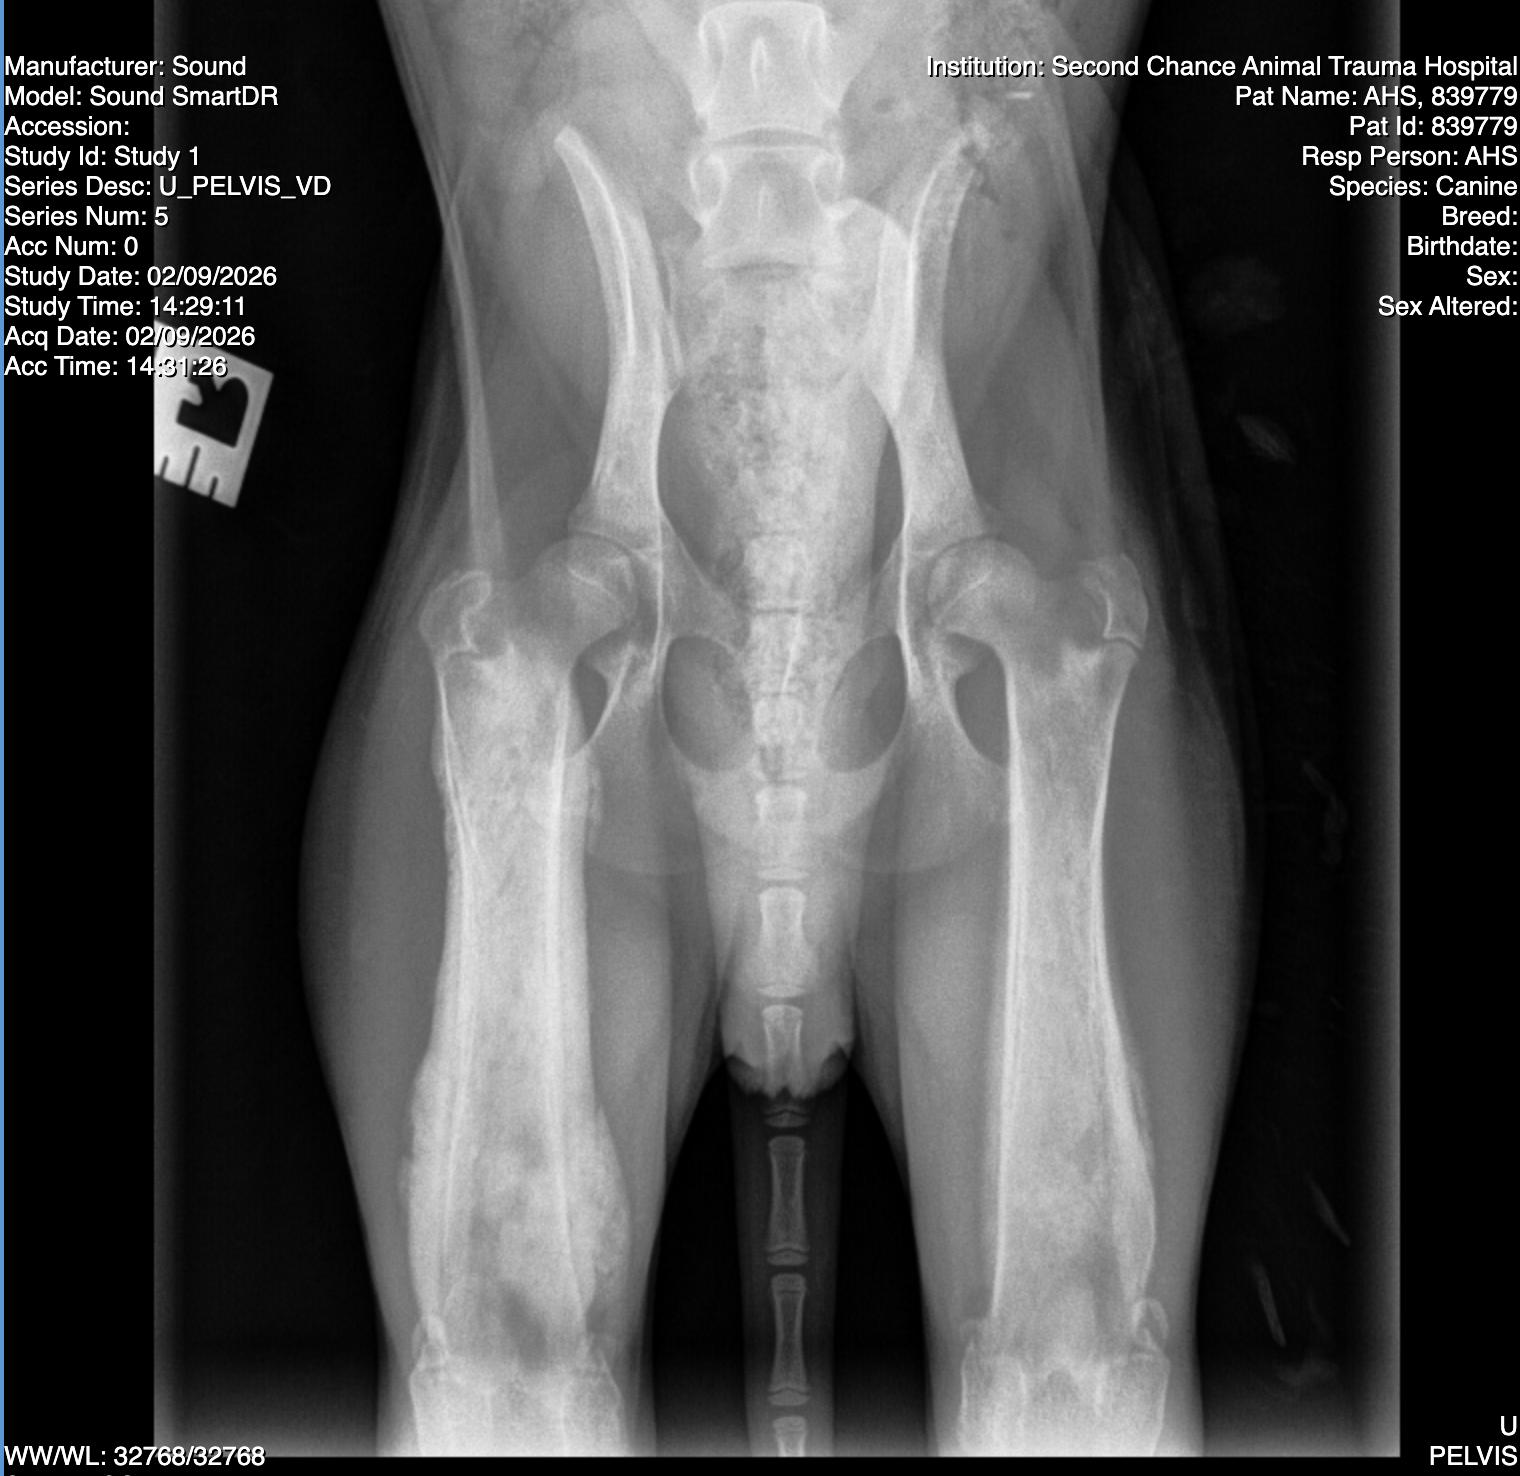

Jetty originally came to AZ Humane as part of a hoarding case with fur so matted that it was shaved. He also had the craziest leg x-rays that ended up being diagnosed as panosteitis - the equivalent of growing pains. He was hurting so bad because he somehow got the worst case of this our vets had ever seen!

Jetty is now well-managed on NSAIDs and it is amazing what a difference they have made. This painful sad puppy has turned into a joyful, playful, happy-go-lucky guy who just loves life! He will need to be on the NSAIDs for a while, but thankfully carprofen is very affordable. He should outgrow this condition when he reaches full maturity - usually by 1.5-2yrs old it's a thing of the past. He has no longterm health concerns, and we even did repeat bloodwork to confirm his initial anemia was gone (it is). He's so healthy!